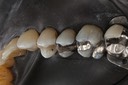

Ted Kanamori #18-19 pre-op